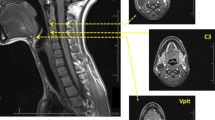

MRI

Three-dimensional coronal oblique T2-weighted images (TE/TR = 87.8/3,000 ms, TI = 0 ms, flip angle = 90°, acquisition matrix = 288 × 192 × 36, reconstruction matrix = 512 × 512 × 36, field of view [FOV] = 160 × 160 mm2, slice thickness = 3 mm, voxel size = 0.31 × 0.31 × 3.00 mm3) were acquired on a 3-T GE HDx scanner (GE Healthcare, Waukesha, WI, USA) with an 8-channel head coil. While T1-weighted images provide high-resolution anatomical images, T2-weighted images provide superior contrast. Because the CSA for each muscle was manually traced using electronic calipers, high-resolution T2-weighted images were selected to provide greater differentiation of the muscle boundaries. Participants were supine in the MRI scanner, with the head and neck placed within the head coil fixed to the scan table. Participants were asked to remain stationary and inhibit swallowing for the duration of the 3-min scan.